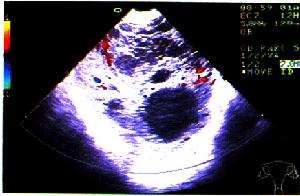

2.超聲診斷 良性囊性畸胎瘤的超聲所見常可分為以下幾種類型:

(1)類囊型:多為圓形或橢圓形囊壁較厚,多為單房,內為密集而反光強的光點,有時在內壁處可見一薄層液性區。

(2)囊內麵團征:囊內出現一個或數個反光強的光團,多為圓形,也有不規則光塊,可黏貼於內壁,光團後方無回聲。

(3)囊內發團征:囊內可見一圓形光團,其上方呈月牙形反光強的回聲,其後方衰減並伴明顯聲影(為脂類物團塊包裹一團毛髮構成)。

(4)囊內脂液分層征:上層為反光強密集光點回聲,此為一層脂類物;下層常為清亮液,有時亦可見液內漂浮少量光點兩層之間為脂液分層平面,較大的囊腫其液平面可隨體位變動而變化。

(5)複雜型:囊內結構複雜,可有光點脂液分層、強光團、發團征及麵團征等。